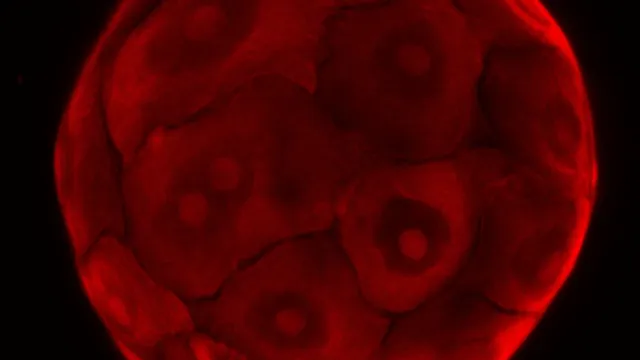

Bij zijn werk aan de rol van het afweersysteem bij darmkanker stuitte Clevers min of meer bij toeval op de stamcellen van waaruit de darmen zichzelf constant vernieuwen. Hij was immunoloog, bezig met de moleculaire signalen die cellen ertoe aanzetten te delen en vond een universeel signaal. Daarmee stond zijn werk aan de basis van de regeneratieve geneeskunde die zich nu aan het ontwikkelen is. De belofte: het lichaam repareren met eigen cellen. Misschien door organen buiten het lichaam te laten groeien, of in varkens. Of levende pleisters te maken die aangedane plekken weer gezond maken.

Geneticus Hans Clevers onderzoekt hoe stamcellen kunnen worden gebruikt om ziek of versleten weefsel te genezen of te vervangen. Dat gaat de wereld veranderen.

‘Voor biologen is een gekweekt mini-orgaantje gewoon een klompje cellen’